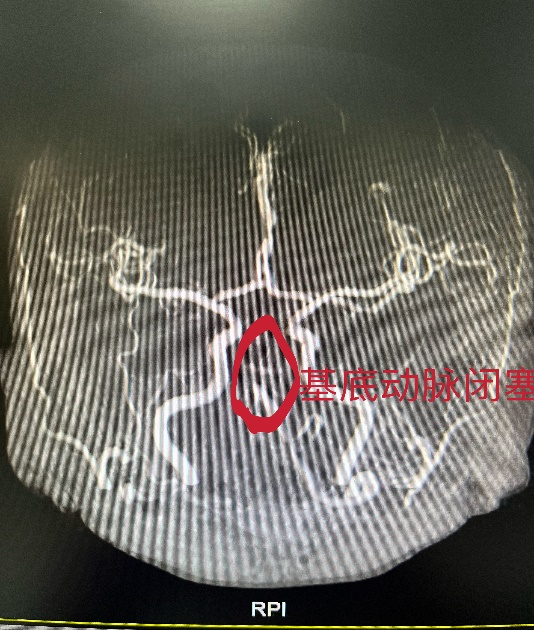

确定不再关注此人吗

4月30日清晨,市五院神经内分泌科一阵急促的电话铃打破了清晨的安静,一名患者起床后突发头晕,言语含混,右侧肢体无力,意识逐渐模糊,请我科急会诊,任桥桥医生立即前往查看病人,考虑患者为急性脑血管病,立即行头颅CT未见出血,在磁共振室的配合下进一步行颅脑MRI+DWI+MRA,发现患者为急性脑干梗死,基底动脉闭塞。基底动脉闭塞可能随时导致患者昏迷,心跳、呼吸骤停,是急性脑梗死中的危重病例,经过匹配考虑患者在溶栓时间窗内,立即启动静脉溶栓,溶栓过程中患者症状一度好转,意识清楚,言语流利,对答切题,肢体无力明显好转,但很快患者又出现言语含混,嗜睡,为挽救患者生命,经柴旭兵主任和吕安林教授讨论后考虑患者病情危重,需急诊行血管内治疗,经患者家属知情同意后,立即启动卒中介入手术治疗,介入室医护接到电话后第一时间到达医院,在介入室的配合下,患者很快行全脑血管造影术,术中发现患者血管情况不容乐观,供应后循环的右侧椎动脉闭塞,左侧椎动脉重度狭窄,基底动脉次全闭塞,经患者家属同意,行基底动脉支架植入,经过复杂的手术过程后,基底动脉支架成功植入,血流恢复通畅,患者意识逐渐好转,术后安返病房后给予进一步积极对症治理,经过及时有效的抢救,现患者神志清,言语流利,四肢肌力正常,已可以下地自行活动。急性脑梗死在最短的时间内开通血管,减少了患者的致残、致死率,提高了患者的生活质量!